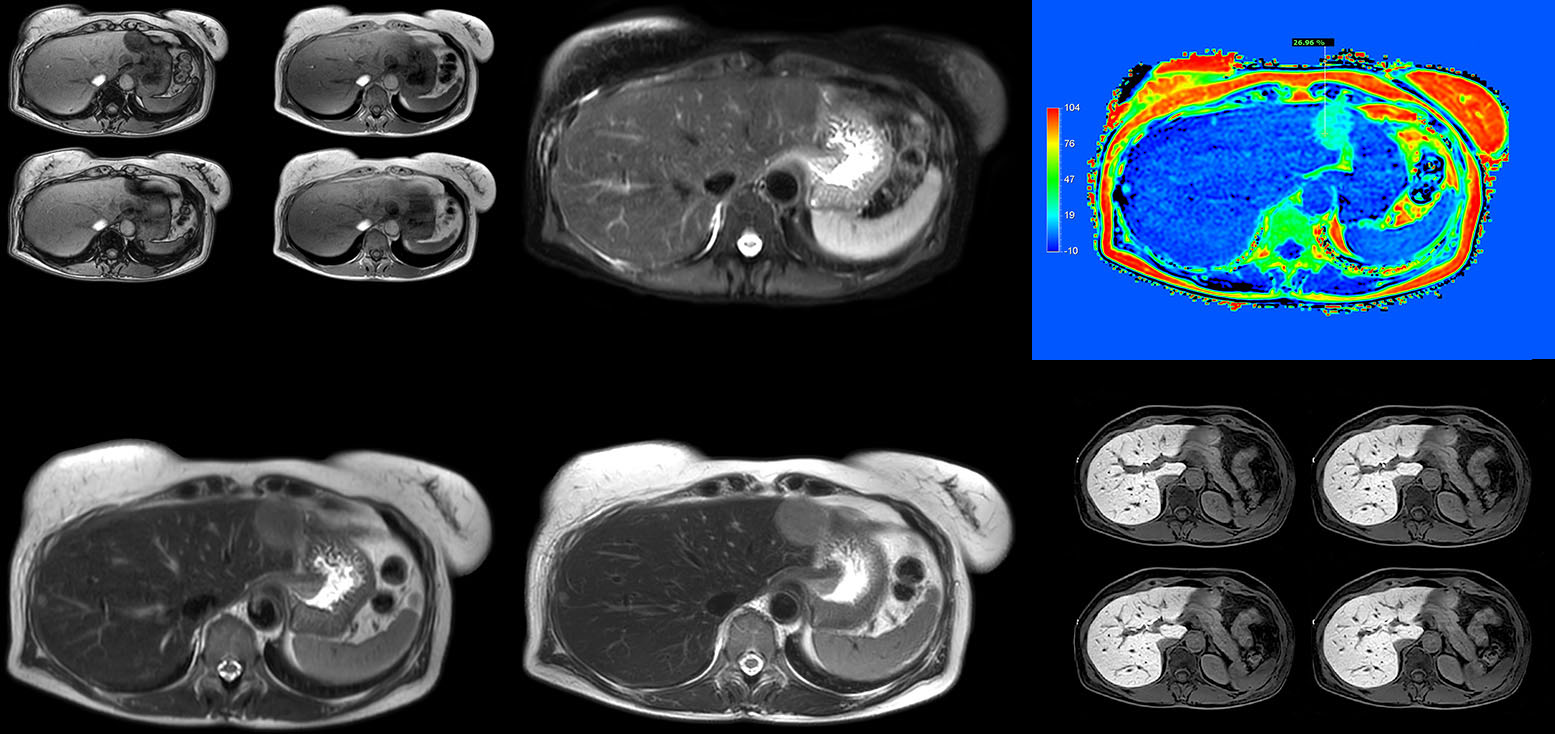

Dr. Kukuk scans an increasing number of liver patients in an arms-up position using the integrated Posterior coil and a special positioning device. “By placing the patient’s arms up, the field of view in the right-left direction can be smaller so that a right-left preparation direction can be used to cut down the scan time,” he explains. “We can use high dS SENSE factors for TSE imaging, so we can shorten the echo train length. This results in a faster scan than arms-down T2 TSE and the images show high anatomical detail.”

“For DWI, the high dS SENSE factor allows using a shorter TE so we get higher signal and fewer susceptibility artifacts, which means less distortion of diffusion weighted images. Of course, with higher dS SENSE factors and the shortening of the TSE factor in T2-weighted imaging, we can drastically cut down the complete examination time. So, with arms-up we get faster images, less distortion in DWI and less blurring on T2-weighted images. Almost all patients tolerate the arms-up scanning well.”